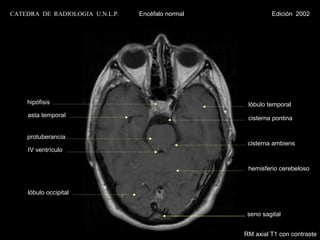

CATEDRA DE RADIOLOGIA U.N.L.P.   Encéfalo normal            Edición 2002

hipófisis                                       lóbulo temporal

asta temporal                                   cisterna pontina

protuberancia

cisterna ambiens

IV ventrículo

hemisferio cerebeloso

lóbulo occipital

seno sagital

RM axial T1 con contraste